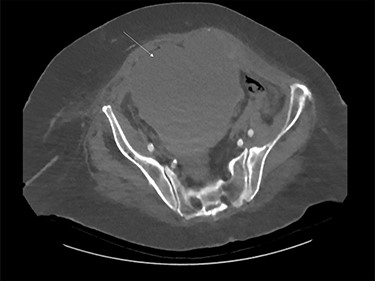

A previously well 82-year-old female was referred for surgical opinion with worsening abdominal pain and loose bowel motions, after being anticoagulated (enoxaparin 90 mg twice daily) for 6 days under the medical team with new onset atrial fibrillation secondary to lower leg cellulitis. Relevant background includes hypertension and type two diabetes. Within 5 h of initial review, patient developed sudden haemodynamic collapse (systolic pressure 86 mm Hg, haemoglobin decreased from 114 g/L to 84 g/L and lactate raised to 13.5 mmol/L). Urgent computed topography showed a large right RSH measuring 151 × 137 × 128 mm extending into space of Retzius without contrast extravasation (Fig. 1). Due to concerns for active bleeding, an emergency radiological intervention by vascular team was arranged.

Large rectus sheath haematoma on computed tomography (white arrow).